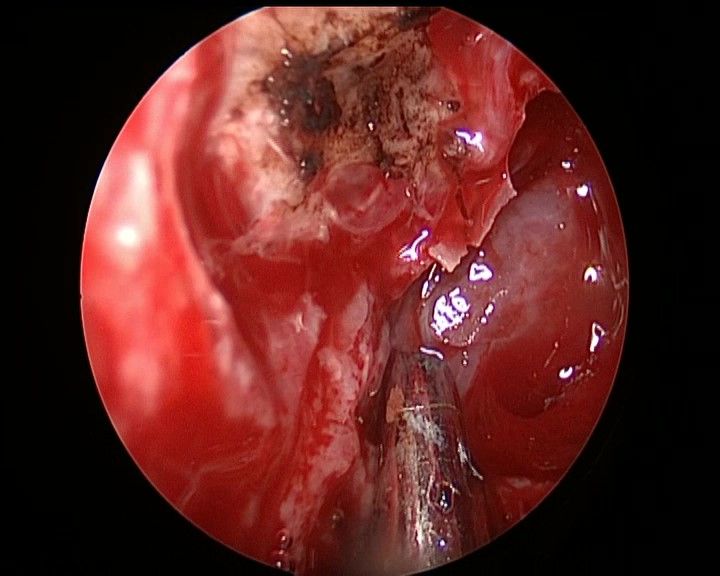

↑ 去除双侧筛窦,观察完整蝶窦前壁